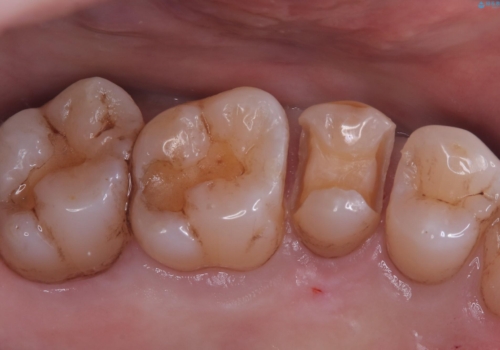

- 主訴:海外に行く前に虫歯があるなら全部しっかり治したい。

右上5番にう蝕があり、審美性・適合性・材料安定性の高いセラミックインレーでのやり替えとなりました。

右上5番の近遠心にう蝕が認められたため、CR裏層の後MOD窩洞のセラミックインレーとしました。